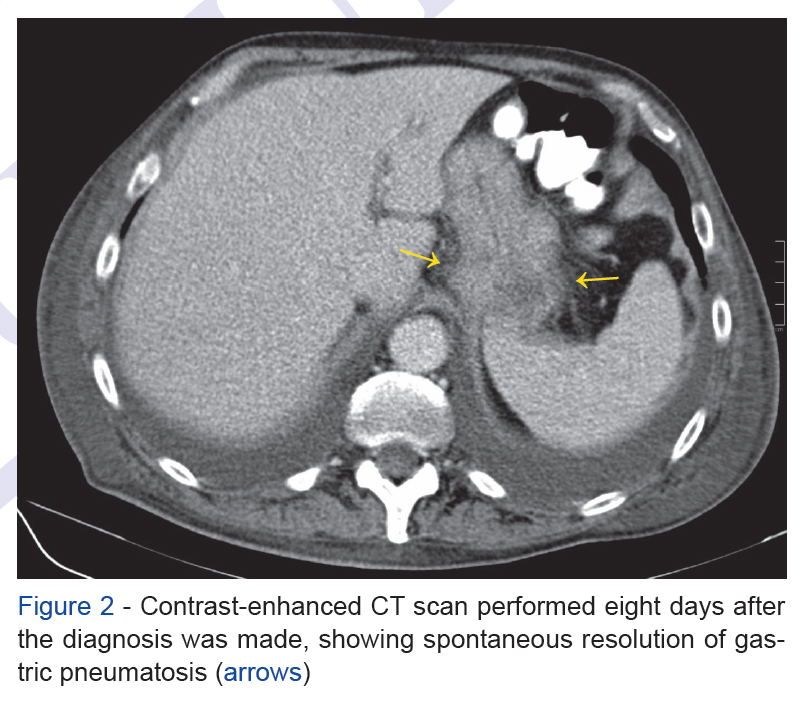

A 78 year-old man, being studied for wasting syndrome with unspecific symptoms, performed a contrast-enhanced computed tomography (CT) scan, revealing stomac...